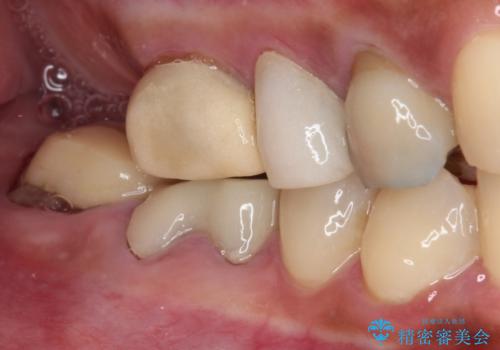

- 奥歯を治療しようと他院で開始したものの、放置してしまったとのことで来院された患者様です。

外れてしまった銀歯や穴の空いた仮歯などあり、適合の悪い被せものと合わせて、セラミッククラウンやセラミックインレーにて治療と行うこととしました。

億劫に感じて治療を先延ばししていたそうですが、始めてみるとスムーズに治療が終わり、早く始めておけば良かったと仰っていました。

他にも加療の必要な歯があるので、定期健診を行いながら再開していく予定です。